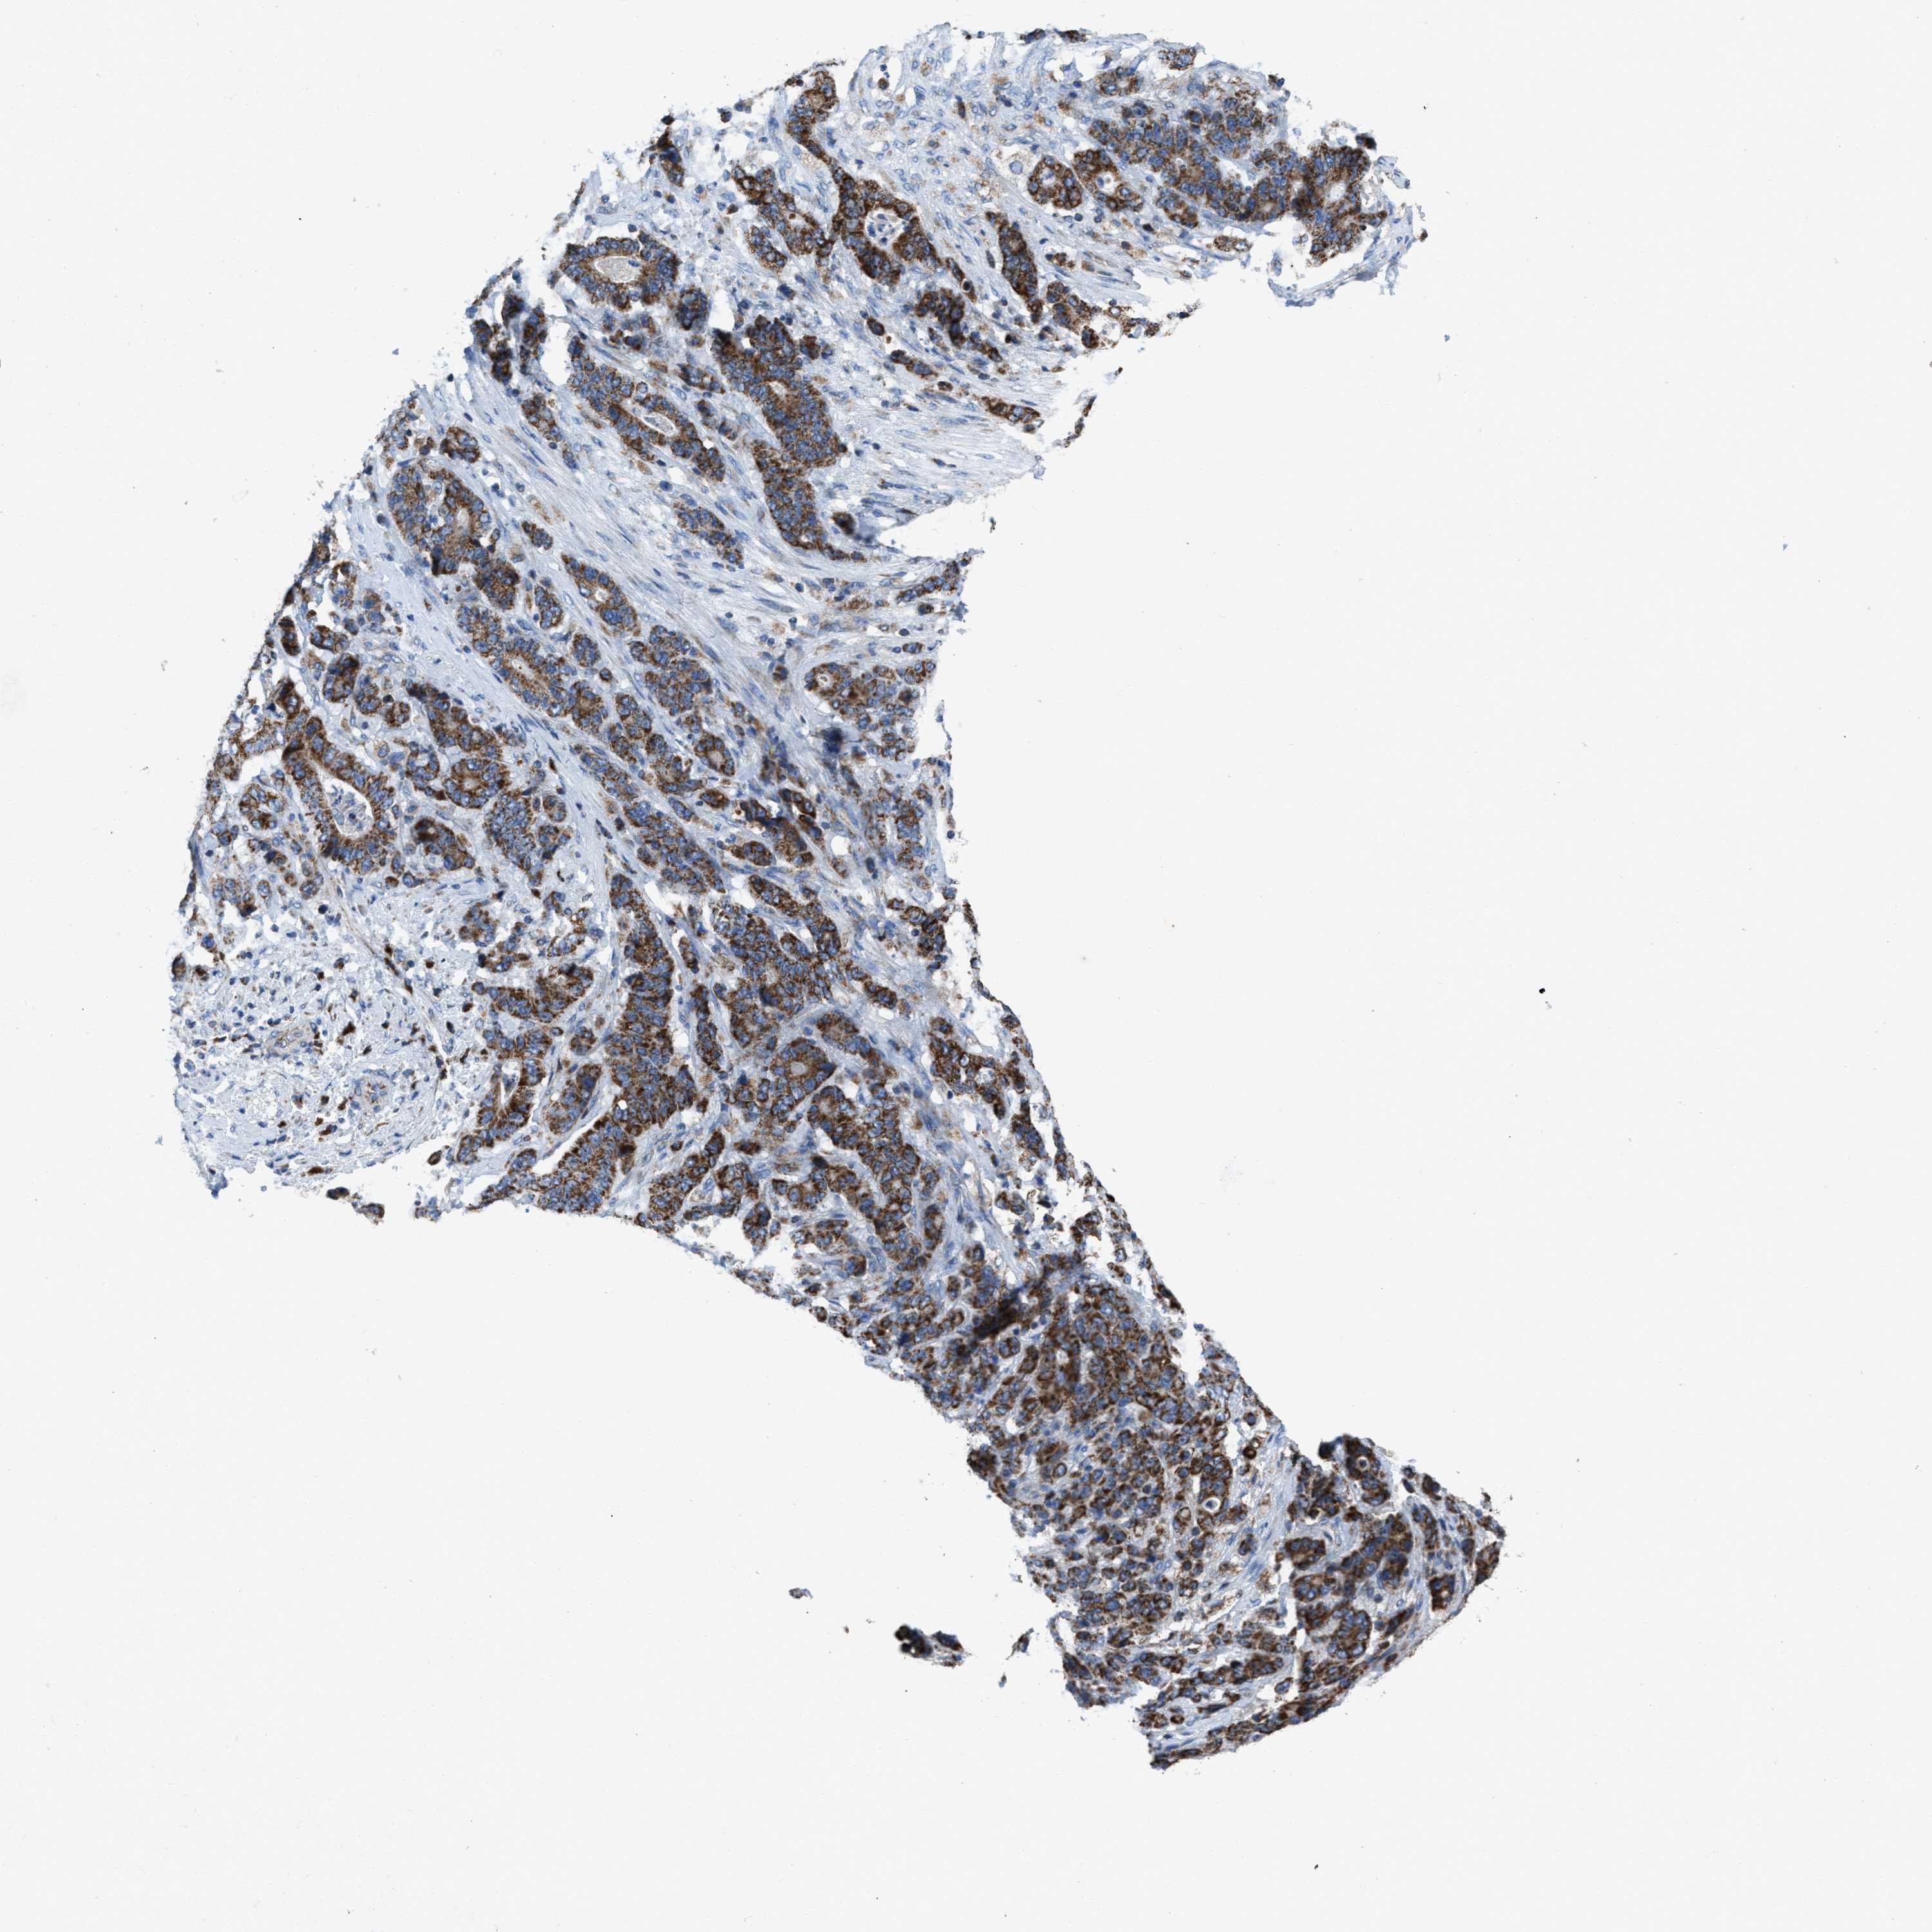

STOMACH CANCER - Protein expressioni

A mouse-over function shows sample information and annotation data. Click on an image to view it in a full screen mode. Samples can be filtered based on level of antibody staining by selecting one or several of the following categories: high, medium, low and not detected. The assay and annotation is described here.

Note that samples used for immunohistochemistry by the Human Protein Atlas do not correspond to samples in the TCGA dataset.

Antibody stainingi

Antibody staining in the annotated cell types in the current human tissue is reported as not detected, low, medium, or high, based on conventional immunohistochemistry profiling in selected tissues. This score is based on the combination of the staining intensity and fraction of stained cells.

Each image is clickable and will lead to virtual microscopy that enables deeper exploration of all samples and also displays staining intensity scores, fraction scores and subcellular localization as well as patient and tissue information for each sample.

Antibody HPA018910

Antibody HPA018921

Antibody HPA018923

Staining

High

Medium

Low

Not detected

Intensity

Strong

Moderate

Weak

Negative

Quantity

>75%

75%-25%

<25%

None

Location

Nuclear

Cytoplasmic/membranous

Cytoplasmic/membranous,nuclear

Adenocarcinoma, NOS